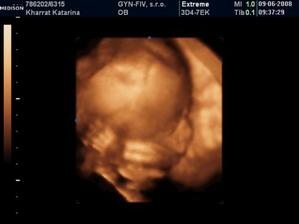

kharratka

28. jan 2008

Amirka, naša vytúžená princezná sa narodila 1.10.2008

Nič krajšie nás nemohlo postretnúť :o)